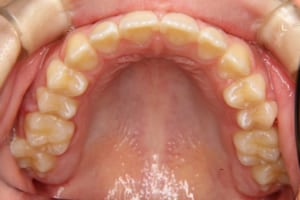

治療後

• 子供の矯正治療のみで並びました

• 子供の矯正治療のみで終了できました

• 子供の矯正歯科治療後です

その他/備考 叢生の程度も中程度でしたが、子どもの矯正治療だけで終了することが出来て、本人も親御さんも大変満足していただけました。